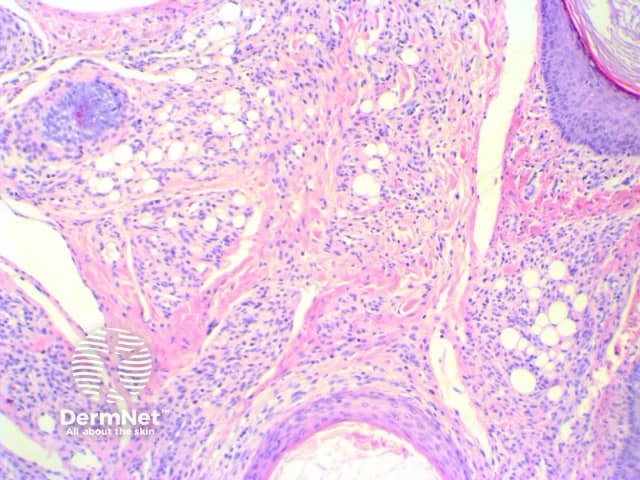

Scanning view shows dilated follicular structure or structures, with radiating mature sebaceous lobules (figures 1, 2). Surrounding the distorted hair follicles there may be thin anastomosing epithelial strands (figure 3). The stroma surrounding the epithelial units is frequently composed of dense collagenous tissue (figure 1-3) and can show prominent clefting to the surrounding adjacent uninvolved dermis (figure 1). Additional stromal changes can include increased vascularity or pockets of adipocytes consistent with increased stromal fat (figure 4).

Figure 4